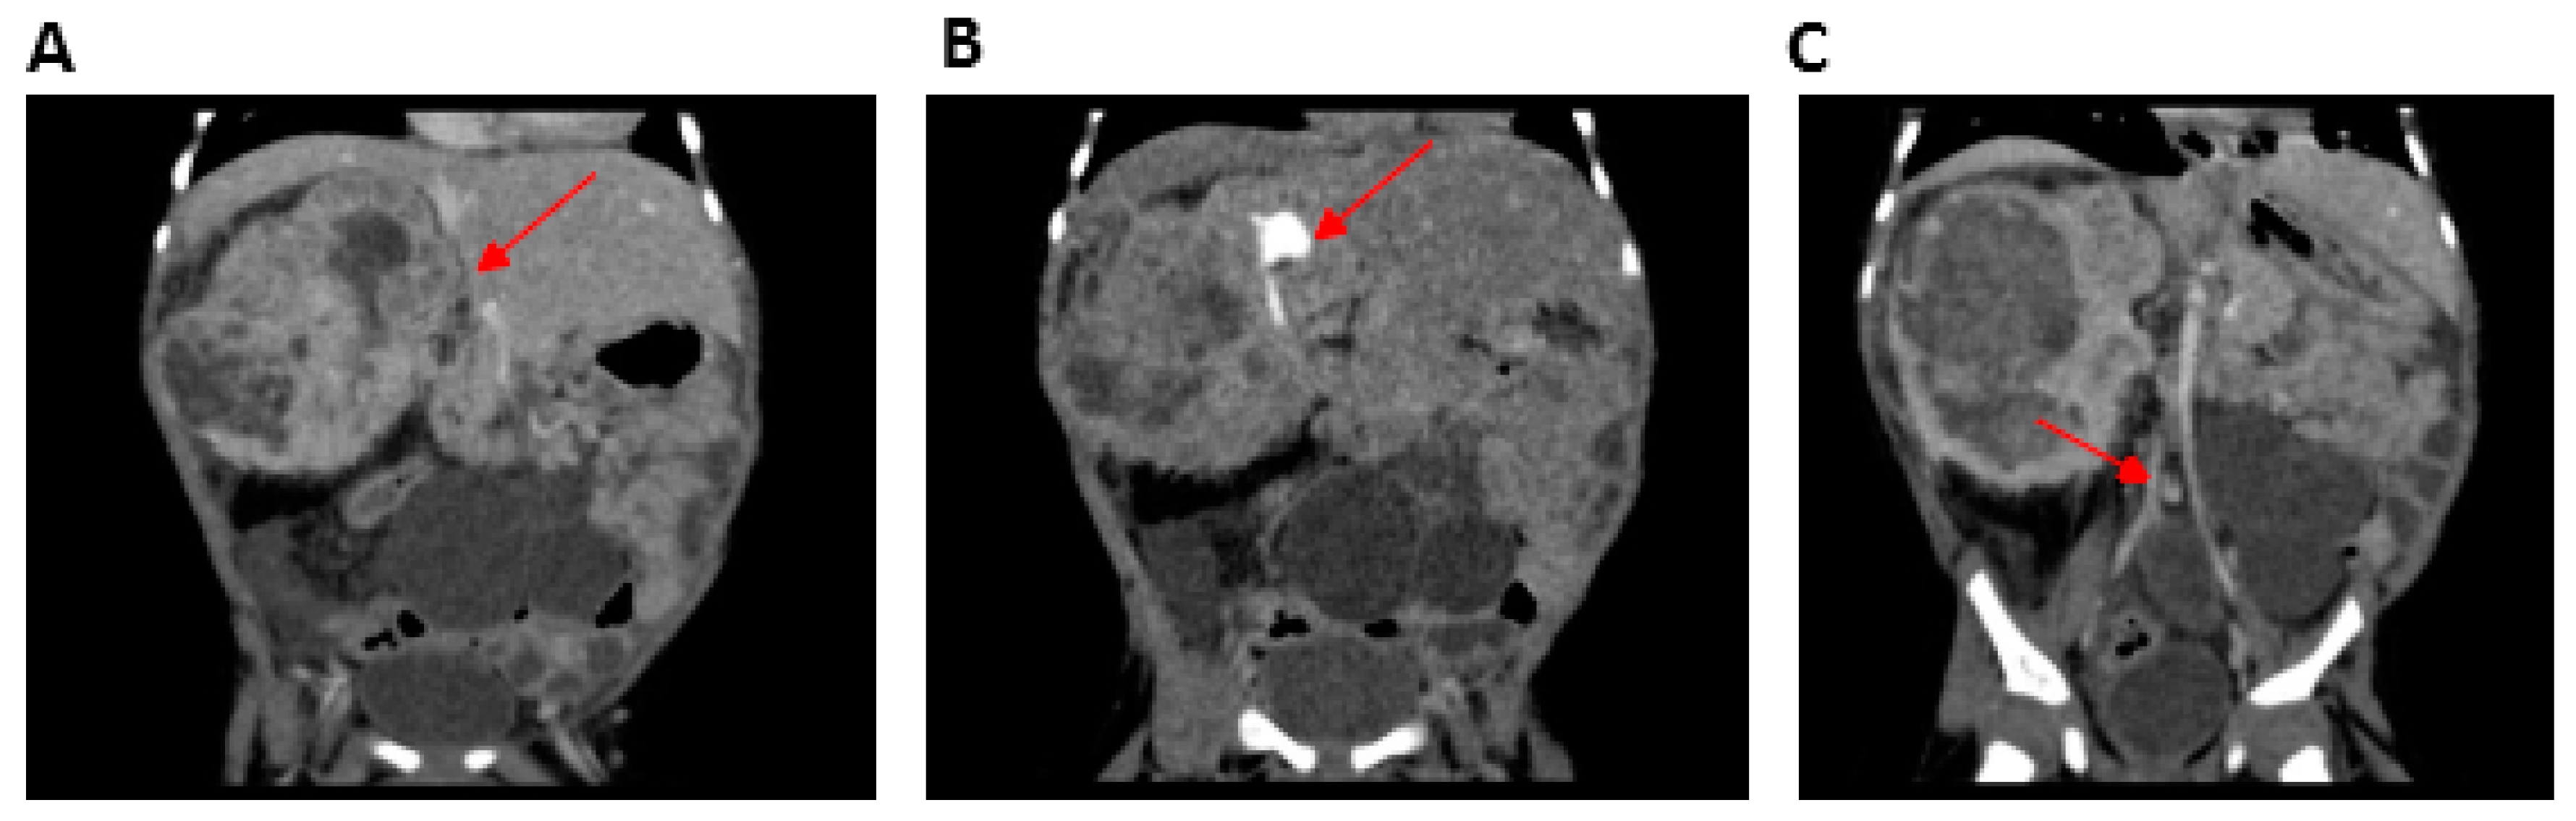

2.1.2. Patient 2 (P2)

| Multicystic kidney | − | + | NR | NR | NR | |

| Mesoblastic nephroma | − | + | − | NR | NR | |